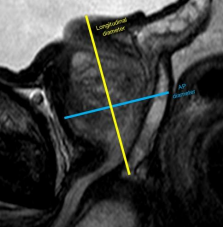

Cáncer de próstata en RM y PI-RADS

Avances en el diagnóstico del cáncer de próstata El cáncer de próstata es una patología muy frecuente en el ámbito clínico, siendo una de las neoplasias más frecuentes en hombres (la segunda neoplasia más frecuente en hombres en Estados Unidos en 2025 según cancer.org). Por lo tanto, son muchos los pacientes con esta patología, o…